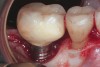

Some amount of microleakage can be expected with any current implant-abutment interface.23,24 External hexagon implants have been found to fail to prevent microleakage.23 Figure 3 and Figure 4 depict an external hexagon implant with an implant-abutment connection vulnerable to microleakage. This same study found internal hexagon implants with internal conical (Morse taper) connection to have the least amount of leakage. Zirconia abutments were found to have more microleakage than titanium abutments. As a result, this study recommended restricting the use of zirconia abutments to cases where esthetic demands are high.23

Fig 3. Clinical and radiographic views of an external hexagon implant restored using a zirconia abutment. The radiograph indicates an implant–abutment connection vulnerable to microleakage. Severe bone loss was due to peri-implantitis.

Figure 3

Fig 4. Clinical and radiographic views of an external hexagon implant restored using a zirconia abutment. The radiograph indicates an implant–abutment connection vulnerable to microleakage. Severe bone loss was due to peri-implantitis.

Figure 4